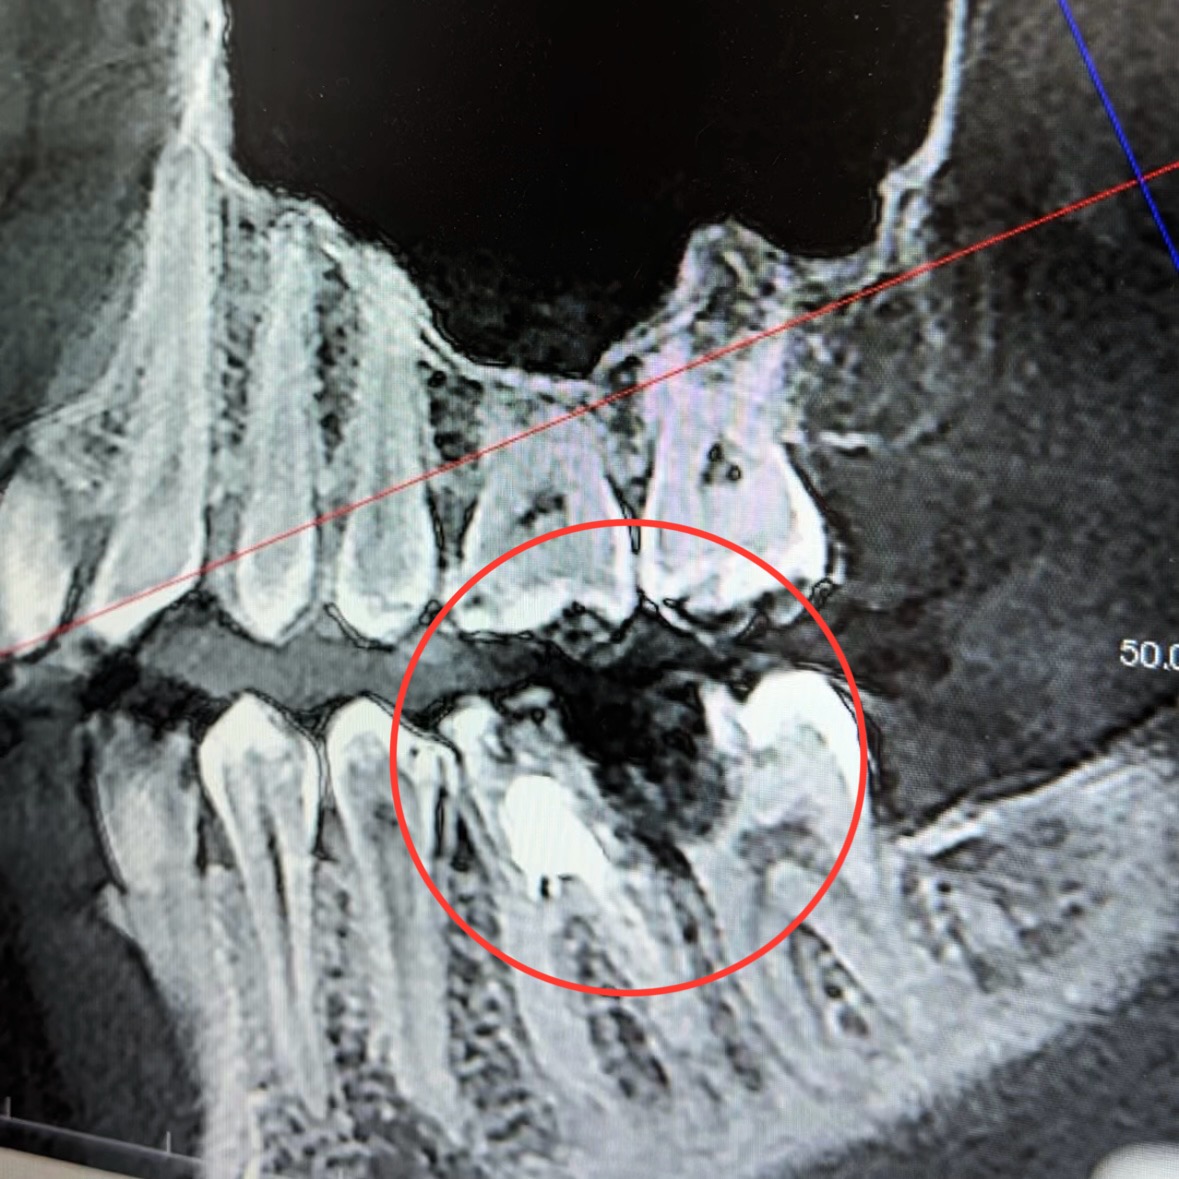

Диагностика

и рентген